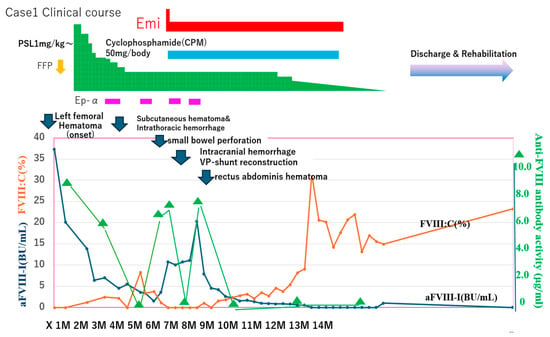

Two and a half months after hospitalization in the Hematology Department, a large subcutaneous hematoma appeared on his left back and chest, complicated by small bowel obstruction (Figure 4 and Figure 5). Eptacog alpha (Ep-α; rhFVIIa, Novo Nordisk, Bagsværd, Denmark) was administered for small intestine resection and massive bleeding. Due to persistent APTT prolongation, emicizumab was administered 3.2 months after hospitalization to achieve stability.

Figure 4.

Clinical course, and FVIII activity and anti-FVIII antibody in case 1” to “FVIII activity, anti-FVIII antibody and anti-FVIII antibody activity in clinical course of case 1. Emi, emicizumab; Ep-α, eptacog alfa; FVIIa, activated clotting factor VII; PSL, prednisolone; FVIII, clotting factor VIII; FVIII:C, FVIII clotting activity; aFIII-I, anti-FVIII inhibitor; BU, Bethesda units; GI, gastrointestinal.

- Anti-FVIII antibody activity in AAFVIII patients (case 1) treated with emicizumab. CWA-sTT could be used to measure anti-FVIII antibody activity in patients treated with emicizumab. Of note, anti-FVIII antibody activity increased significantly during major bleeding and decreased after FVIIa treatment (Figure 4).